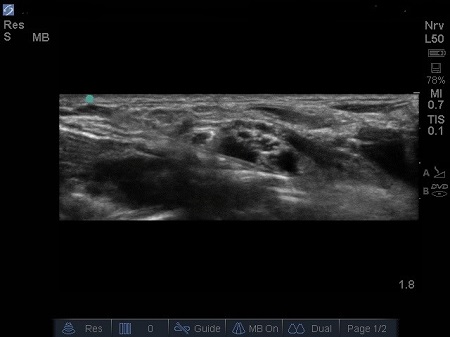

- Local anaesthetic (LA) should spread around the hypoechoic circles causing hydro dissection of the planes. (5) See 6. & 7.

Fig. 7. Increasing spread of LAj

- It may sometimes be necessary to reposition the needle to ensure an adequate distribution of the LA (the entire plexus is surrounded by LA). See Fig. 8.

Fig. 8. Needle withdrawn and re –directed over the superior aspect of the brachial plexus, LA deposited to surround brachial plexus.